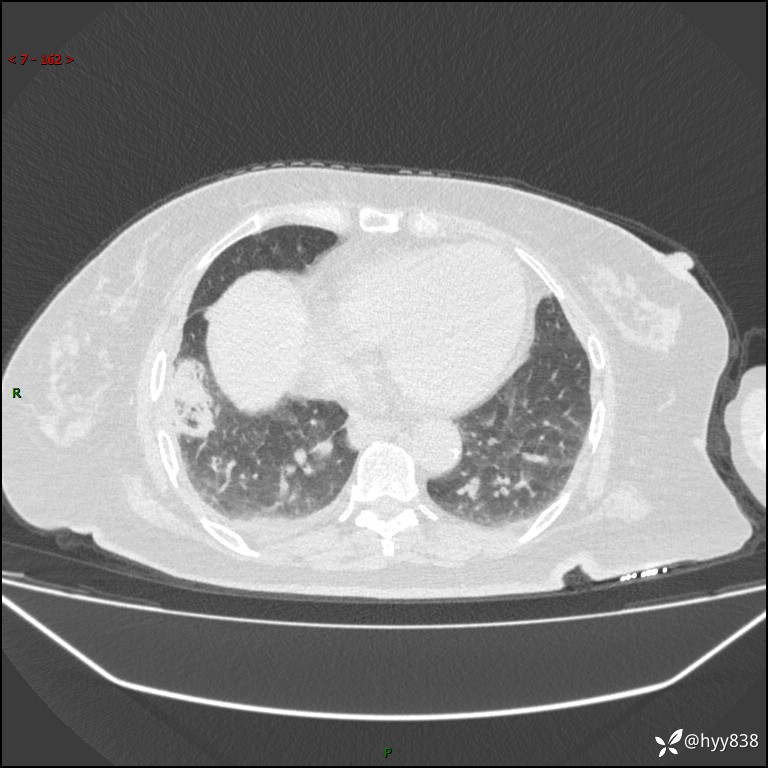

患者性别:女

患者年龄:57岁

简要病史:昏迷入院

临床诊断:昏迷

胸部 CT平扫、